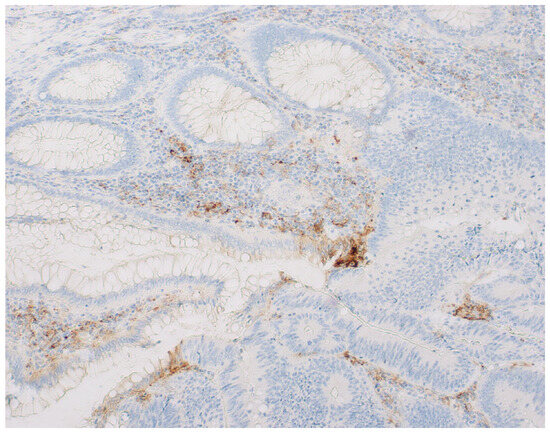

Figure 1. Assessment of the immunohistochemical expression of PD-L1 in colorectal cancer. (A)—PD-L1-positive tumor and immune cells (×400). (B)—tumor and immune cells negative for PD-L1 (×200). (C)—PD-L1-positive immune cells, and negative tumor cells (×200). (D)—PD-L1-positive tumor cells, and negative immune cells (×200).

Figure 2. Image of PD-L1 expression at the border of the transition from normal mucosa to tumor tissue.